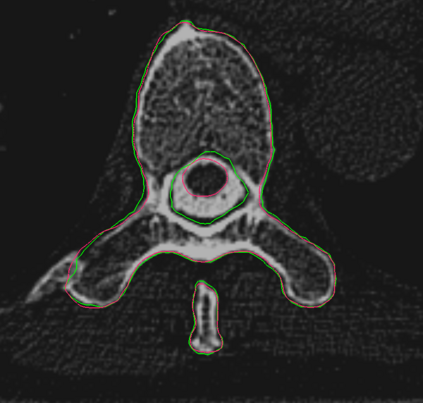

Vertebrae localization, segmentation and identification in CT images is key to numerous clinical applications. While deep learning strategies have brought to this field significant improvements over recent years, transitional and pathological vertebrae are still plaguing most existing approaches as a consequence of their poor representation in training datasets. Alternatively, proposed non-learning based methods take benefit of prior knowledge to handle such particular cases. In this work we propose to combine both strategies. To this purpose we introduce an iterative cycle in which individual vertebrae are recursively localized, segmented and identified using deep-networks, while anatomic consistency is enforced using statistical priors. In this strategy, the transitional vertebrae identification is handled by encoding their configurations in a graphical model that aggregates local deep-network predictions into an anatomically consistent final result. Our approach achieves state-of-the-art results on the VerSe20 challenge benchmark, and outperforms all methods on transitional vertebrae as well as the generalization to the VerSe19 challenge benchmark. Furthermore, our method can detect and report inconsistent spine regions that do not satisfy the anatomic consistency priors. Our code and model are openly available for research purposes.